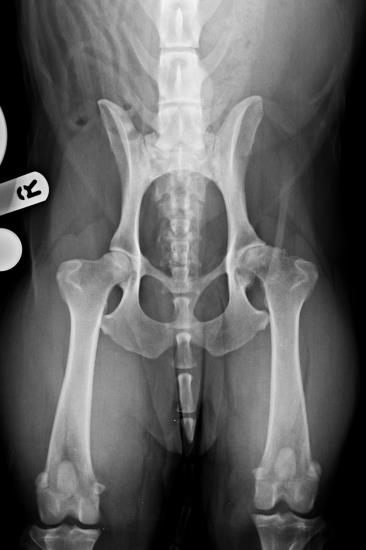

Marley a seven-year-old male English Springer Spaniel was presented with a history of progressively worsening hind limb lameness secondary to arthritis of the left hip.

Pre-operative ventrodorsal radiograph of the pelvis showing osteoarthritis of the left hip joint